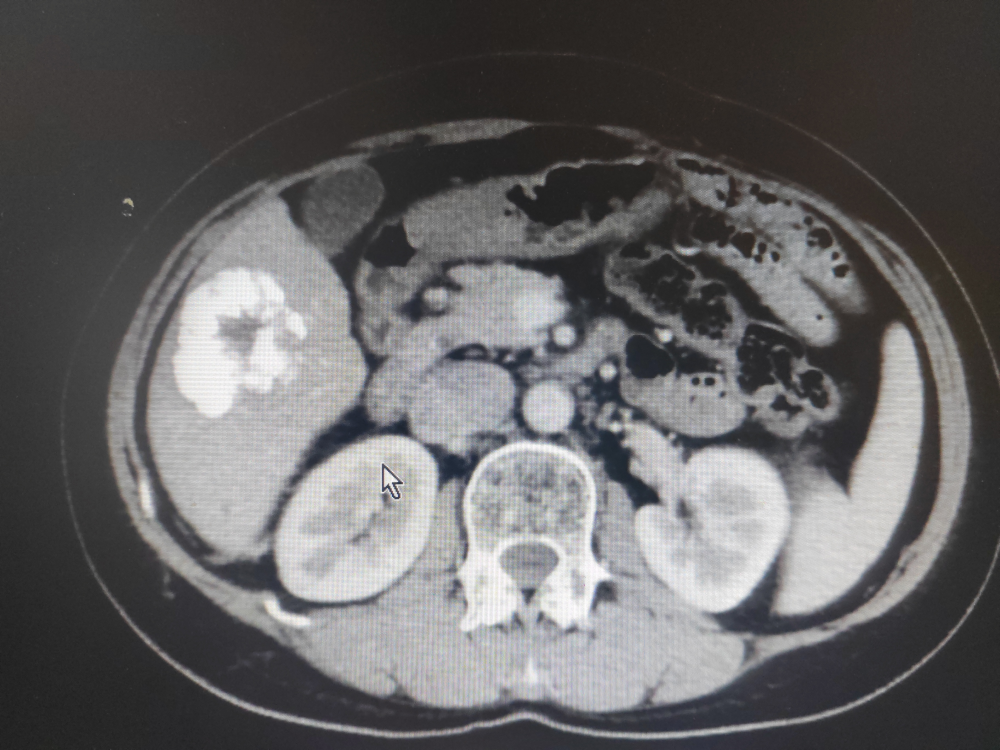

患者劉某,男,47歲,因腹痛於2022年1月17日在我院門診就(jiù)診,門診CT示:1、慢(màn)支肺氣腫及慢性炎症;2、右上(shàng)肺小結節,建議3-6個月(yuè)複查,3、掃及髒內異常密度灶建議必要時進一步檢查。當即轉往江西省腫瘤醫院就診,完善檢查,診斷為原發性肝癌,當時予以TACE術及卡瑞利珠單抗聯合多納菲尼靶向治療。2022年3月6日為行免疫治療前往我院內三(sān)科住院治療,完善檢查示:上腹部增強CT示:肝VI段及V段腫塊並碘(diǎn)油沉(chén)積,係介入治療術後改變,肝V段病(bìng)灶大部分存活,肝VI段病灶小(xiǎo)部分存活:肝I1 段小結節並(bìng)異常強化考慮小血管瘤:肝內多發(fā)微囊(náng)腫,肝門及腹(fù)膜後多(duō)發稍大(dà)淋巴結。甲胎蛋白(bái)異質體:322.82ng/ml個甲胎蛋白(bái):818.02ng/ml個甲胎蛋白異質體比率:40.09%完善術前檢查於2022 年3月10日在南昌(chāng)大學(xué)第(dì)一附屬(shǔ)醫院羅榮光副主任醫師指導下,內(nèi)三(sān)科肖緒銀副(fù)主任醫師、柯於鋒副主任醫師、盧軍主治醫師(shī)完成了我院首例經導管(guǎn)肝癌栓塞術,術後恢複良好,此後(hòu)患者定期行免(miǎn)疫治療。此後定期複查病情穩(wěn)定,2023年4月15日(rì)CT示:與2022年10月25日上腹部CT平掃(sǎo)及增(zēng)強比(bǐ)較:1、肝VI段及V段腫塊並碘油沉積,係介(jiè)入治療術後改變,腫塊大致相仿,未見明確強化,隨診(zhěn)複查(chá)。2、肝段小(xiǎo)結節(jiē)並異常強化,考慮小血管瘤肝內多發微囊腫:肝門及腹膜(mó)後多發稍大淋巴結;均較前片變化不(bú)著。3、脾前緣無明顯強化低密度灶,同前。4、右腎(shèn)微小結石。2023年4月16日(rì)甲(jiǎ)胎蛋(dàn)白:9.39ng/ml1療效評價大PR。

2022年3月7日上腹部增強CT